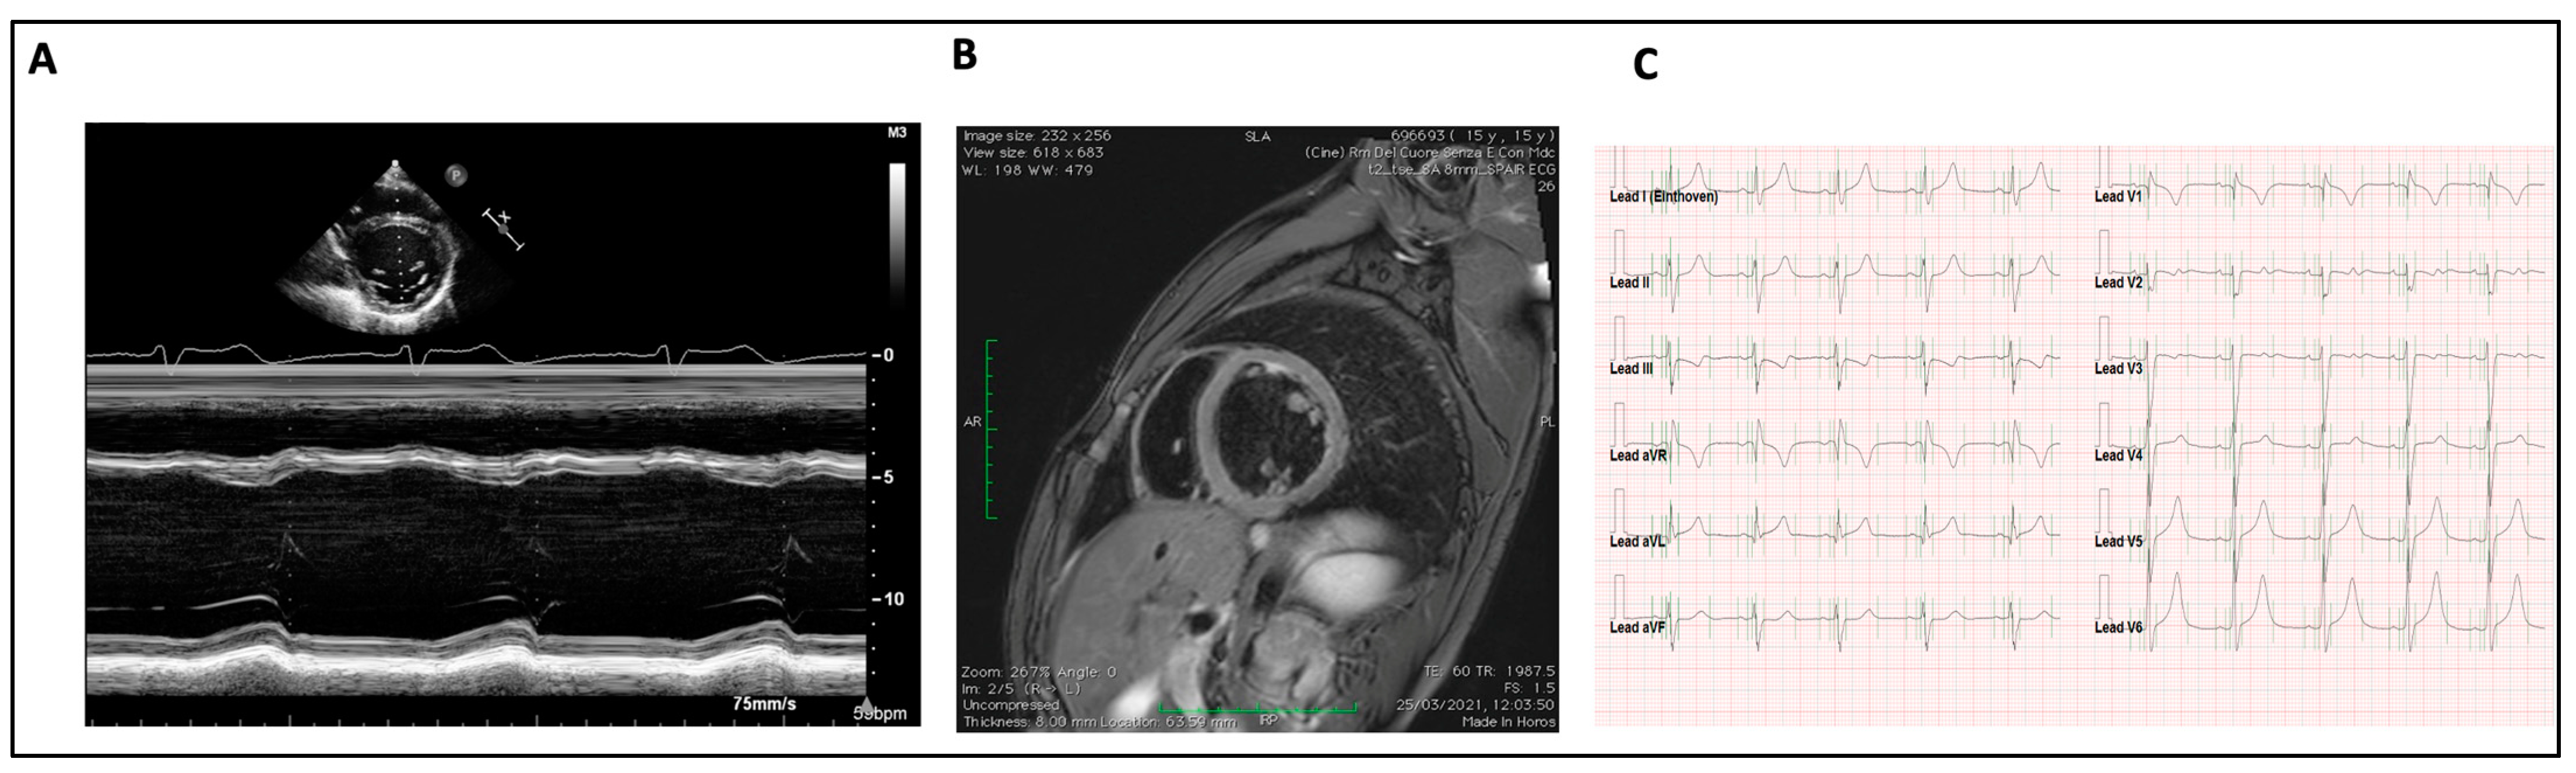

- Dilated cardiomyopathy (DCM) was diagnosed in the presence of increased ventricular end-diastolic diameter (>2 Z-Score) associated with any degree of systolic dysfunction, defined as impaired left ventricular ejection fraction (EF). EF was measured by the biplane Simpson method (normal value: >55%, mild dysfunction: 45–54%, moderate dysfunction: 30–44%, severe dysfunction: <30%).

| CMP in CI | 20 (33.3%) | 17(85%) | 3 (12%) | 0 | 0 |

| Average EF% at first valuation | 53.3 | 52.76 | 56.7 | 0 | 0 |

| Average EF% at last valuation | 46.9 | 46.4 | 50 | 0 | 0 |